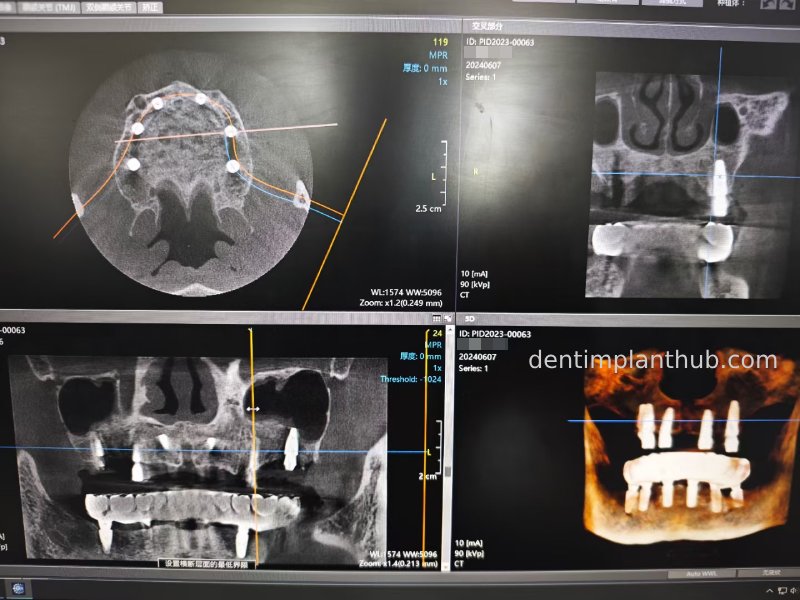

Post-surgical CBCT review photos

16

14

12

22

24

26